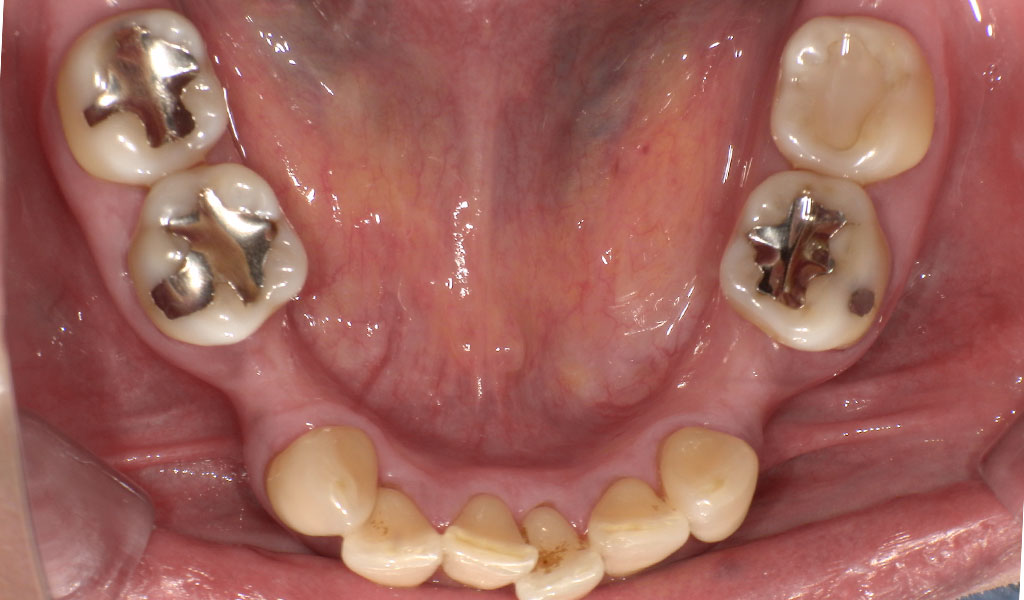

Before4

After4